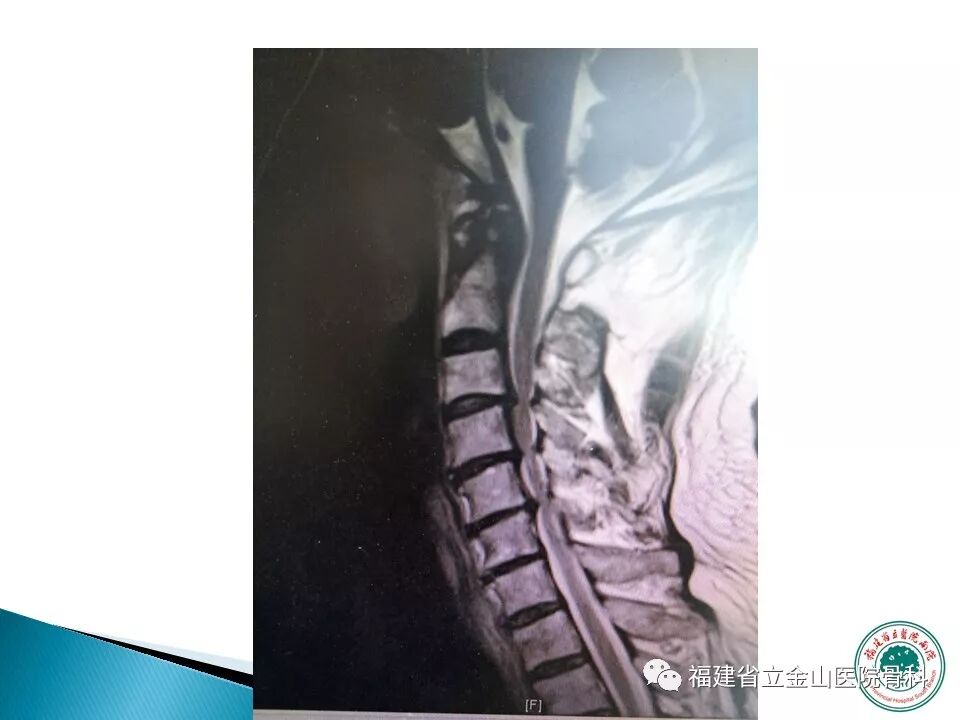

显微镜辅助下颈椎多节段间隙减压

探查硬脊膜无压迫

伊姆有严重的颈椎病,入院时四肢几乎瘫痪,术后半年可以生活自理。